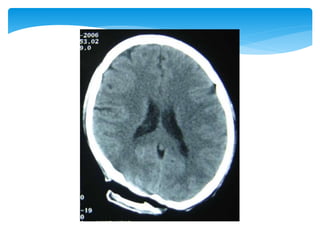

Approach To CT ScanCT scan

Bone window

Look for fractures-

•Cranial vault

•Skull base

•Facial bones

Tissue window

•EDH

•SDH

•ICH

•Contusions

•Pneumocephalus

•Hydrocephalus

•Cerebral edema

Subdural window

•Any hemorrhage

•Soft tissue and bone

•Fontanel

•Suture lines

•Foreign bodies

 Appearance of the normal structures

CT Scan